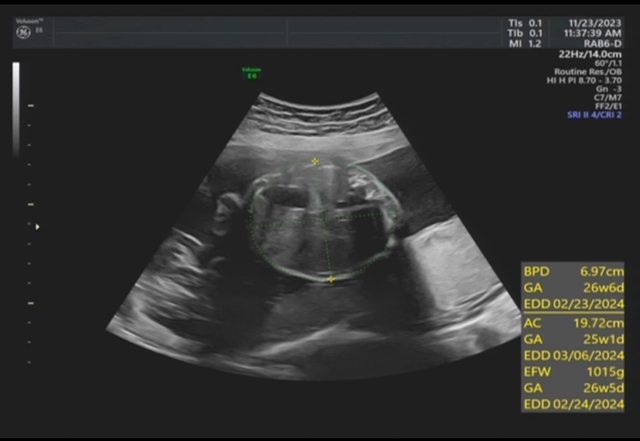

昨天去產檢,醫生覺得寶寶的胃偏大之後要注意觀察 我搜尋了一下好像只有看到胃太小的文,請問大家有沒有遇過類似情況? 我後來看了一下22週的高層次照片,那時候寶寶也是胃大大的,但那時只說是寶寶可能剛 吃飽 https://i.imgur.com/amlKp09.jpg

每一胎的狀況真的不一樣,這次第二胎先歷經羊水少週數小三週,到現在追到剩小一週, 但昨天醫生又提醒胃好像偏大,只希望二寶可以健康平安出生~ -- ※ 發信站: 批踢踢實業坊(ptt-site.org.tw), 來自: 101.12.24.40 (臺灣) ※ 文章網址: https://ptt-site.org.tw/BabyMother/M.1700797726.A.8D2